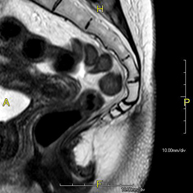

Prueba diagnóstica no invasiva que consiste en la obtención de imágenes de alta definición anatómica de la pelvis mediante el empleo de un campo electromagnético y ondas de radio (con un emisor y un receptor). No utiliza radiación ionizante. Se realiza para estudiar patologías del útero, del ovario, de las trompas y la vagina, ya sean de origen tumoral, inflamatorio o vasculares. Además permite valorar les estructuras adyacentes localizadas en la pelvis, identificando sus alteraciones. A veces requiere el uso de contraste intravenoso (Gadolinio) para caracterizar las lesiones. - RM Pelvis masculina

Prueba diagnóstica no invasiva que consiste en la obtención de imágenes de alta definición anatómica de la pelvis masculina mediante el empleo de un campo electromagnético y ondas de radio (con un emisor y un receptor). No utiliza radiación ionizante. No requiere de preparación previa. En algunas ocasiones requiere el empleo de contraste paramagnético (Gadolinio) para caracterizar las lesiones. Esta prueba permite valorar órganos como la vejiga urinaria, la unión entre los uréteres y la vejiga, la próstata, las vesículas seminales, la uretra, los huesos de la pelvis, etc.